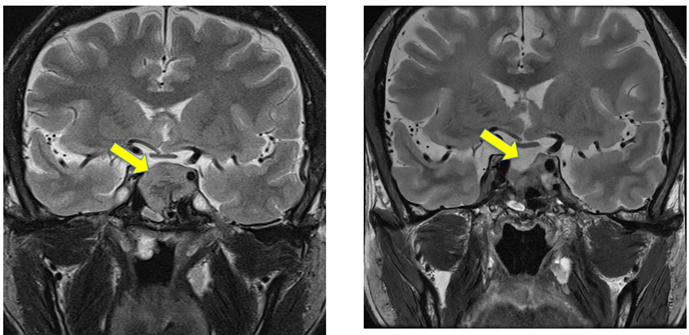

48歲魏先生於健康檢查時發現約2.5公分腦下垂體腫瘤,尚在評估治療方式的期間,突發噁心、嘔吐與呼吸困難等症狀至新陳代謝科住院治療。經檢查發現生長激素過高、血糖控制困難,並一度併發感染性敗血症,進一步檢查確認感染源為肝臟膿瘍,在多重內分泌風暴威脅下,新陳代謝科即時給予對症治療,待病情穩定後,由神經外科及鼻科組成的手術團隊接手,以經鼻內視鏡手術成功切除腦下垂體腫瘤,術後病情穩定,未見復發(如下圖)。

腦下垂體腫瘤 腫瘤摘除後病情穩定無復發